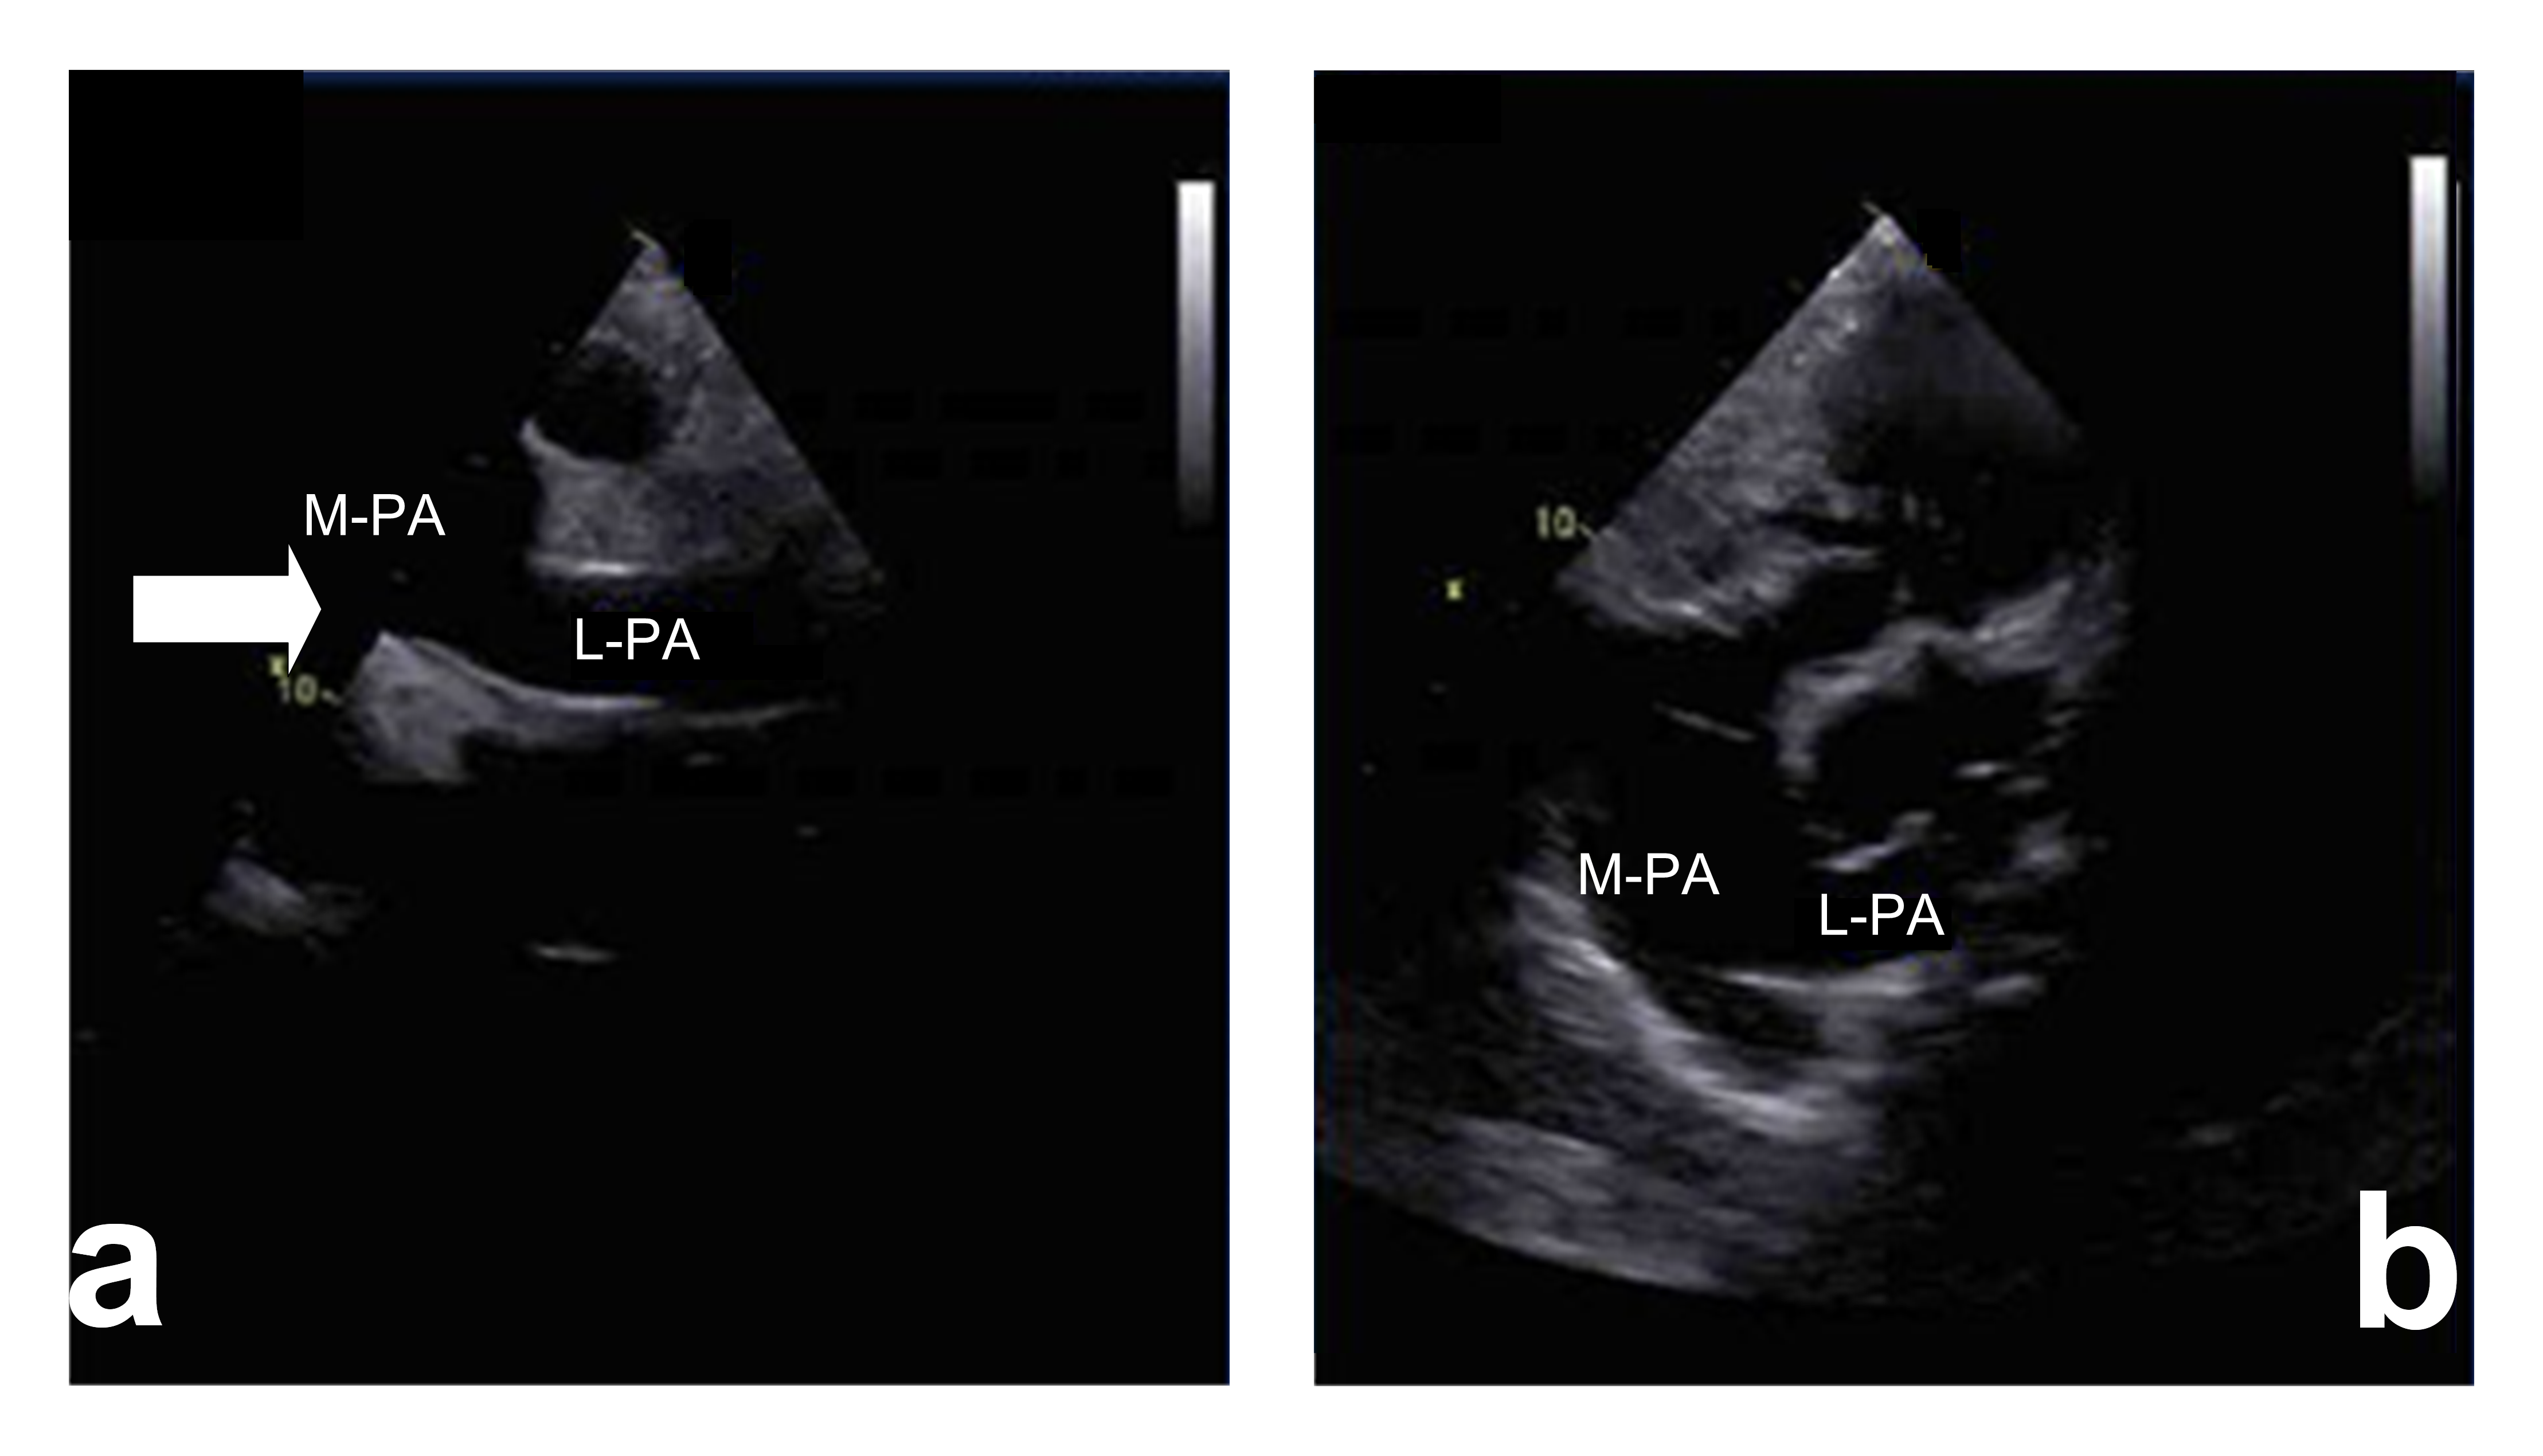

A 3-year-old girl with absent left pulmonary artery complicated with tetralogy of Fallot (TOF) and atrial septal defect (ASD) is shown in Fig. 4 (stenosis group). This three-year-old girl had found out the absence of the left pulmonary artery combined with tetralogy of Fallot and atrial septal defect by echocardiography before congenital heart surgery. Intraoperative findings comfirmed there was no left pulmonary artery emission from the main pulmonary artery. The girl accepted radical correction operation of TOF and the repair of ASD, the pulmonary artery was not treated, echocardiographic postoperative follow-up only.

Fig. 4.Short axis view of great vessels (Color Doppler and 2D image). In this view there is not left pulmonary artery structure from the main pulmonary artery (arrow). PA, main pulmonary artery; LPA, left pulmonary artery; AO, Aorta; RV, right ventricle; RA, right atrium.

In addition, the reasons of ultrasound misdiagnosis in UAPA is mainly due to insufficient caution of this disease during scanning. This may be due to insufficient understanding of the disease or the patient’s image is unclear due to lung disease. If it was found that the pulmonary artery was not clearly displayed in the examination, cardiologists or sonographers should pay attention to scanning the high level short-axis view of the great vessels. Use color Doppler to detect pulmonary artery branch and the situation of the left and right pulmonary artery. According our experience, there were two situation were most easily misdiagnosed: (1) For the left pulmonary artery absence patient, the ductus arteriosus is often misdiagnosed as a pulmonary artery branch (Fig. 1). This may be due to insufficient knowledge of the disease or the operating doctor’s inadequate scanning of the branches of the pulmonary artery. (2) Tetralogy of Fallot (TOF) patients combined with the absence of pulmonary arteries are easily missed also (Fig. 4), the misdiagnosis rate was as high as 77% (7/9), the reason was considered as following: TOF patient’s pulmonary artery branches were usually very thin, which were difficult to detect by 2D echocardiography, and pulmonary stenosis induced blood flow turbulence, which affected pulmonary branch color Doppler imaging.